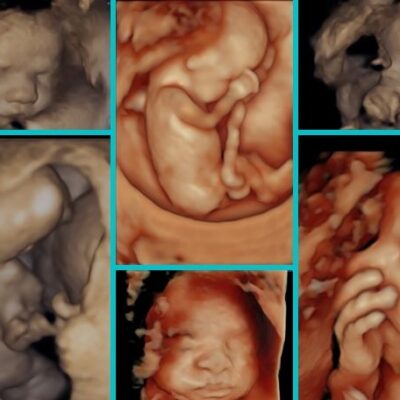

3D/4D Ultrasound Scan

Provides detailed three-dimensional or live video images of your baby, allowing you to see facial features and movements. Enhances visualization for both parents and doctors.